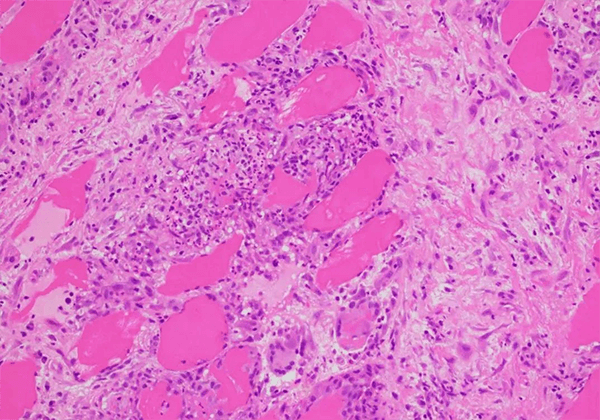

з»“иҠӮз—…жҳҜдёҖз§Қз—…еӣ дёҚжҳҺзҡ„ж…ўжҖ§еӨҡзі»з»ҹзӮҺжҖ§з–ҫз—…�����пјҢзү№еҫҒдёәйқһе№Ій…Әж ·дёҠзҡ®ж ·иӮүиҠҪиӮҝ�����пјҢдјҙжңүеҚ•дёӘж ёз»Ҷиғһжөёж¶Ұе’Ңеҫ®з»“жһ„з ҙжҚҹ�����гҖӮиҜҘз—…еҸҜзҙҜеҸҠзҡ®иӮӨ�����пјҢзңјзқӣ�����пјҢеҝғи„Ҹе’ҢдёӯжһўзҘһз»Ҹзі»з»ҹ�����пјҢеҮҢй©ҫ90%зҡ„з—…дҫӢзҙҜеҸҠиӮәйғЁ�����гҖӮиҜҘз–ҫз—…жҳҜйҮҚеӨ§зҡ„гҖҒжңӘзҹҘи¶ізҡ„еҢ»з–—йңҖжұӮд№ӢдёҖ�����гҖӮ

дҪңдёәйҖҡиҝҮFDAеӯӨе„ҝиҚҜиө„ж ји®Өе®ҡзҡ„ж–°иҚҜ�����пјҢKBMAB-16жҳҜдёҖз§ҚеҲҶеӯҗйҮҸзәҰ149еҚғйҒ“е°”йЎҝзҡ„дәәйј еөҢеҗҲжҠ—иӮҝзҳӨеқҸжӯ»еӣ еӯҗеҚ•е…ӢйҡҶжҠ—дҪ“�����пјҢз”ЁдәҺжІ»з–—з»“иҠӮз—…дјҙжҲ–дёҚдјҙиӮәеӨ–еҸ—зҙҜзҡ„ж–°еһӢз”ҹзү©еҲ¶е“Ғ�����гҖӮзҺ°еңЁе°ҡжңӘжңүжІ»з–—з»“иҠӮз—…зҡ„иӮҝзҳӨеқҸжӯ»еӣ еӯҗ-ОұжҠ‘еҲ¶еүӮиҺ·жү№�����пјҢдҪҶKBMAB-16дҪңдёәиӮҝзҳӨеқҸжӯ»еӣ еӯҗ-ОұжҠ‘еҲ¶еүӮзҡ„зҗҶеҢ–жҖ§еӯҗе’ҢиҚҜзҗҶдҪңз”Ёе·ІдёҫиЎҢдәҶеӨ§е®—з ”з©¶�����гҖӮ